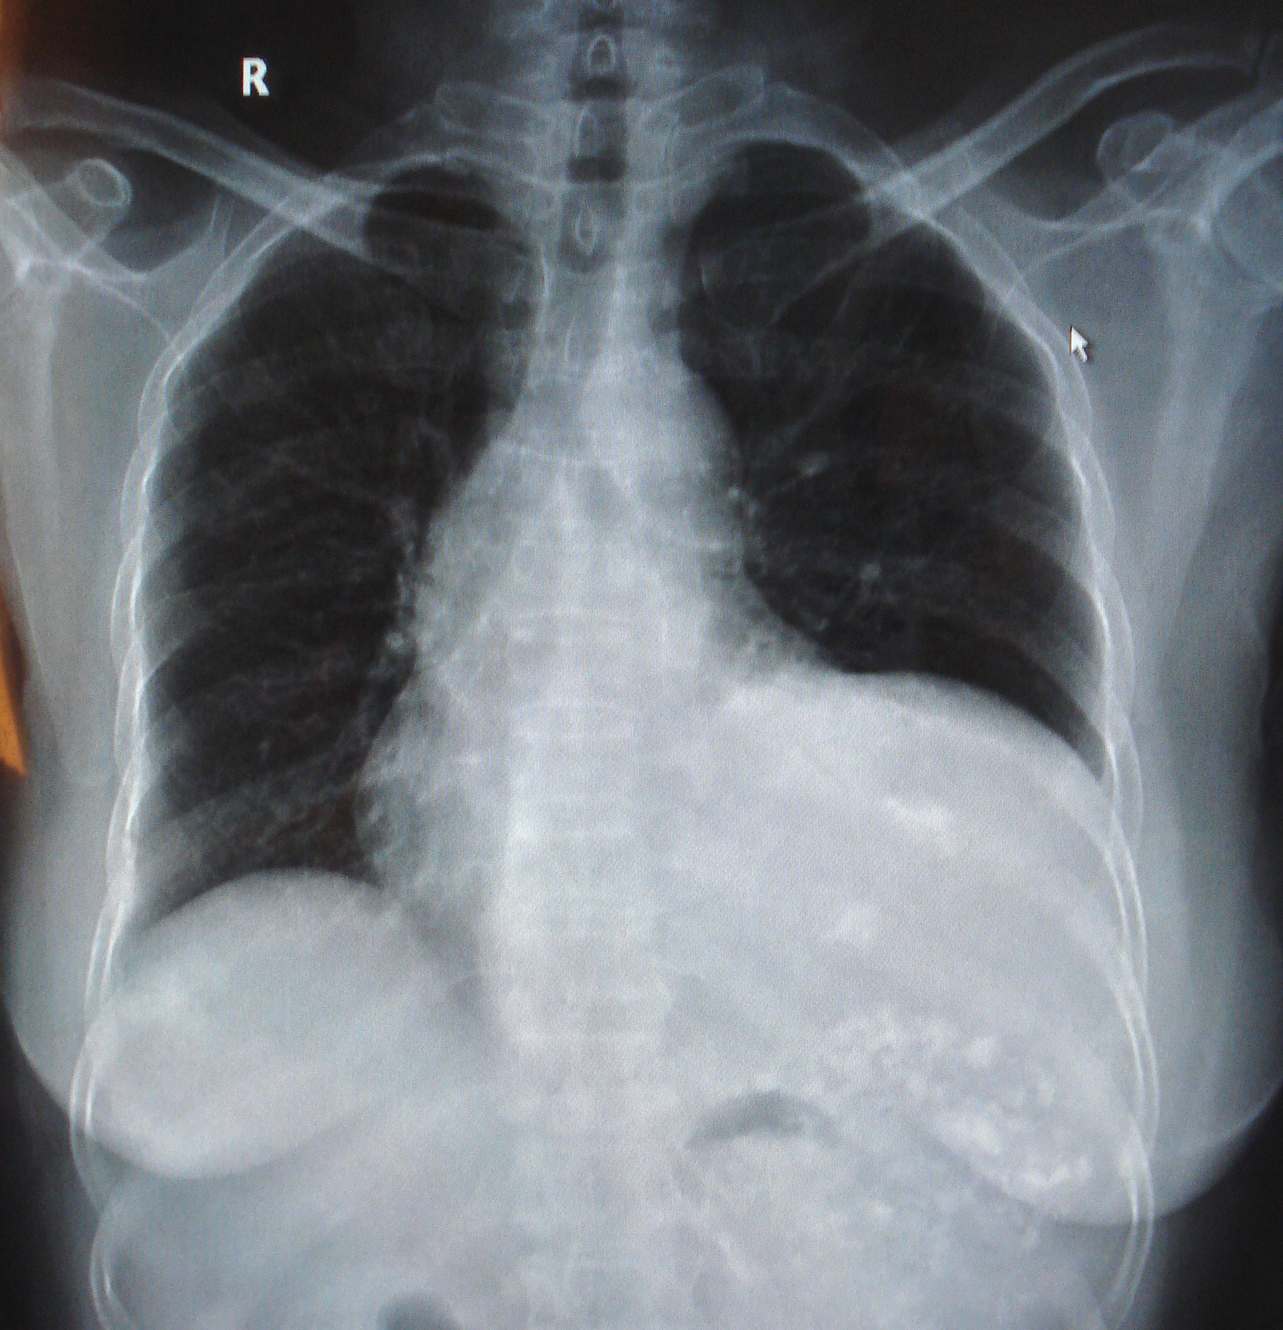

异常胸片图片

异常胸片图片,

间隔肺癌胸片筛查时受病理类型和部位的影响

正常胸片和患新冠肺炎胸片的不同.

胸片正位